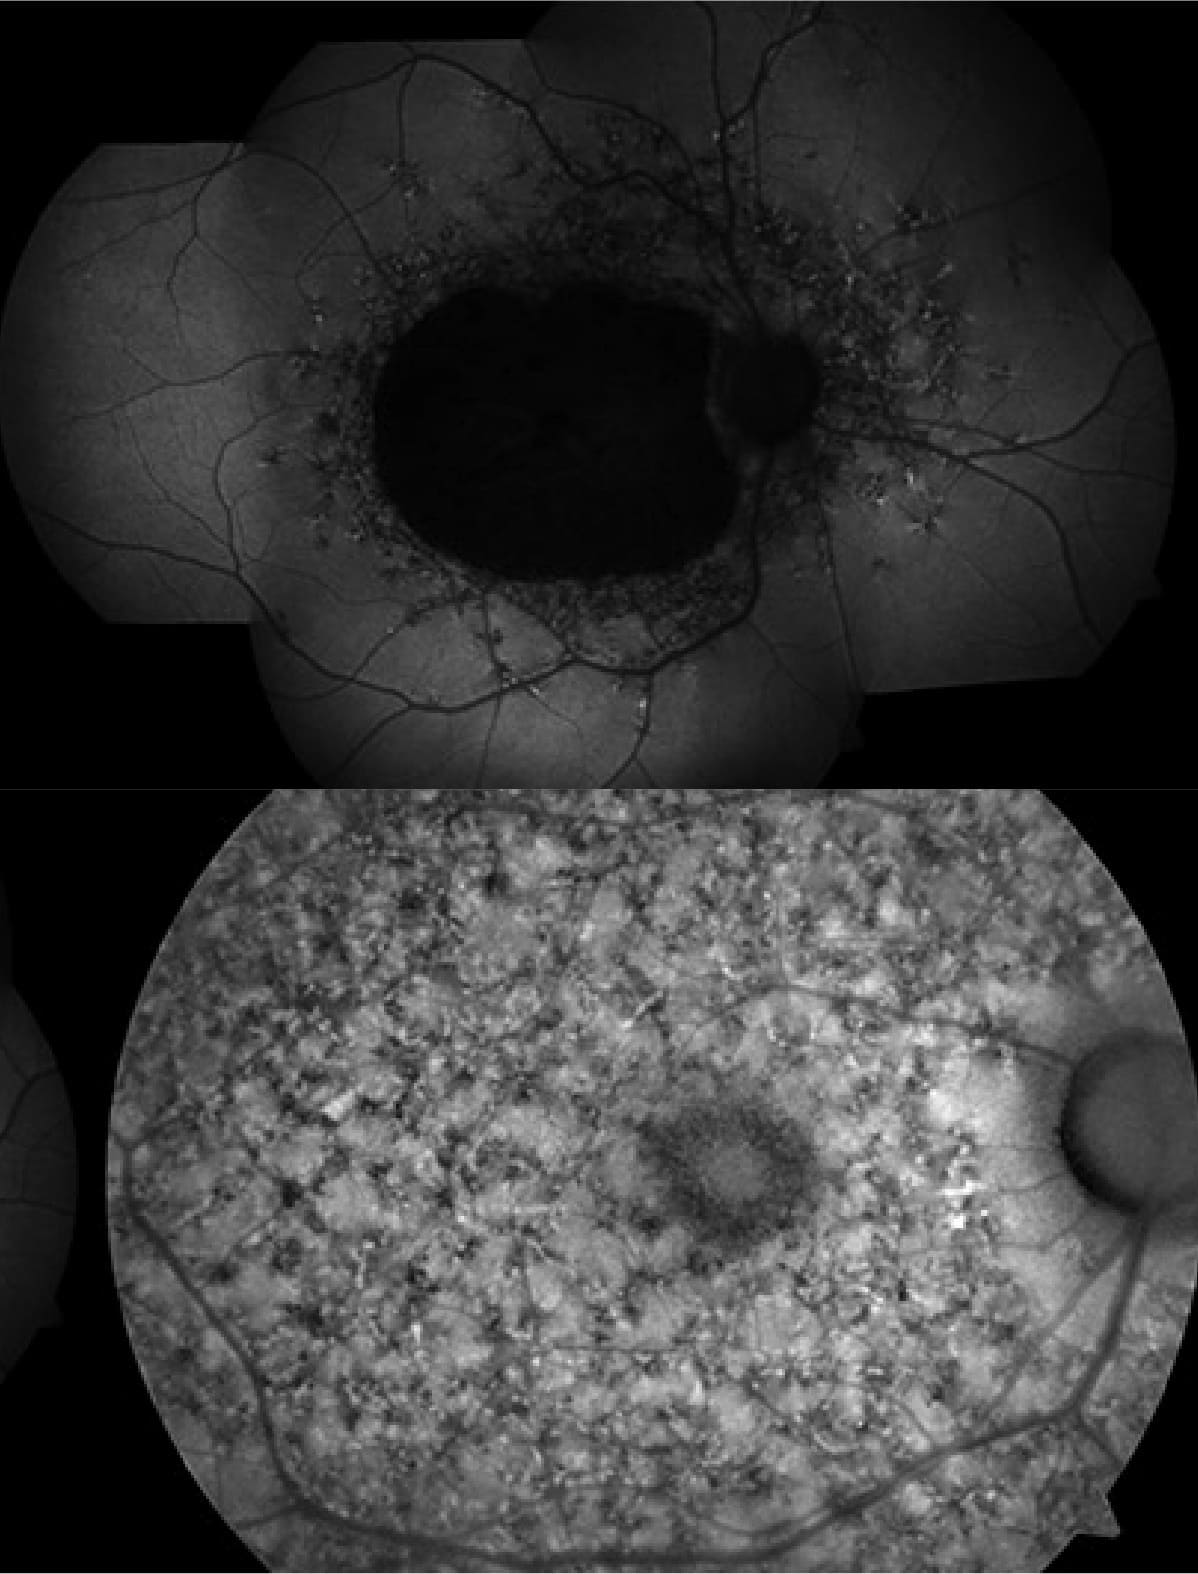

Distrofia en la retina fondo de ojo

Distrofia en retina y mácula

No existen síntomas visuales específicos, por lo que una distrofia retiniana suele detectarse durante exploraciones rutinarias del fondo de ojo. Es imprescindible completar el diagnóstico con un examen retiniano mediante tomografía de coherencia óptica de alta resolución y autofluorescencia del fondo de ojo, principalmente.

Para confirmar el diagnóstico y establecer el tipo de distrofia las pruebas habituales solicitadas son: pruebas electrofisiológicas (electrorretinograma, electrooculograma, potenciales evocados visuales), angiografía con fluoresceína sódica, con verde de indociana o mediante OCT (Tomografía de Coherencia Óptica) , así como campo visual.